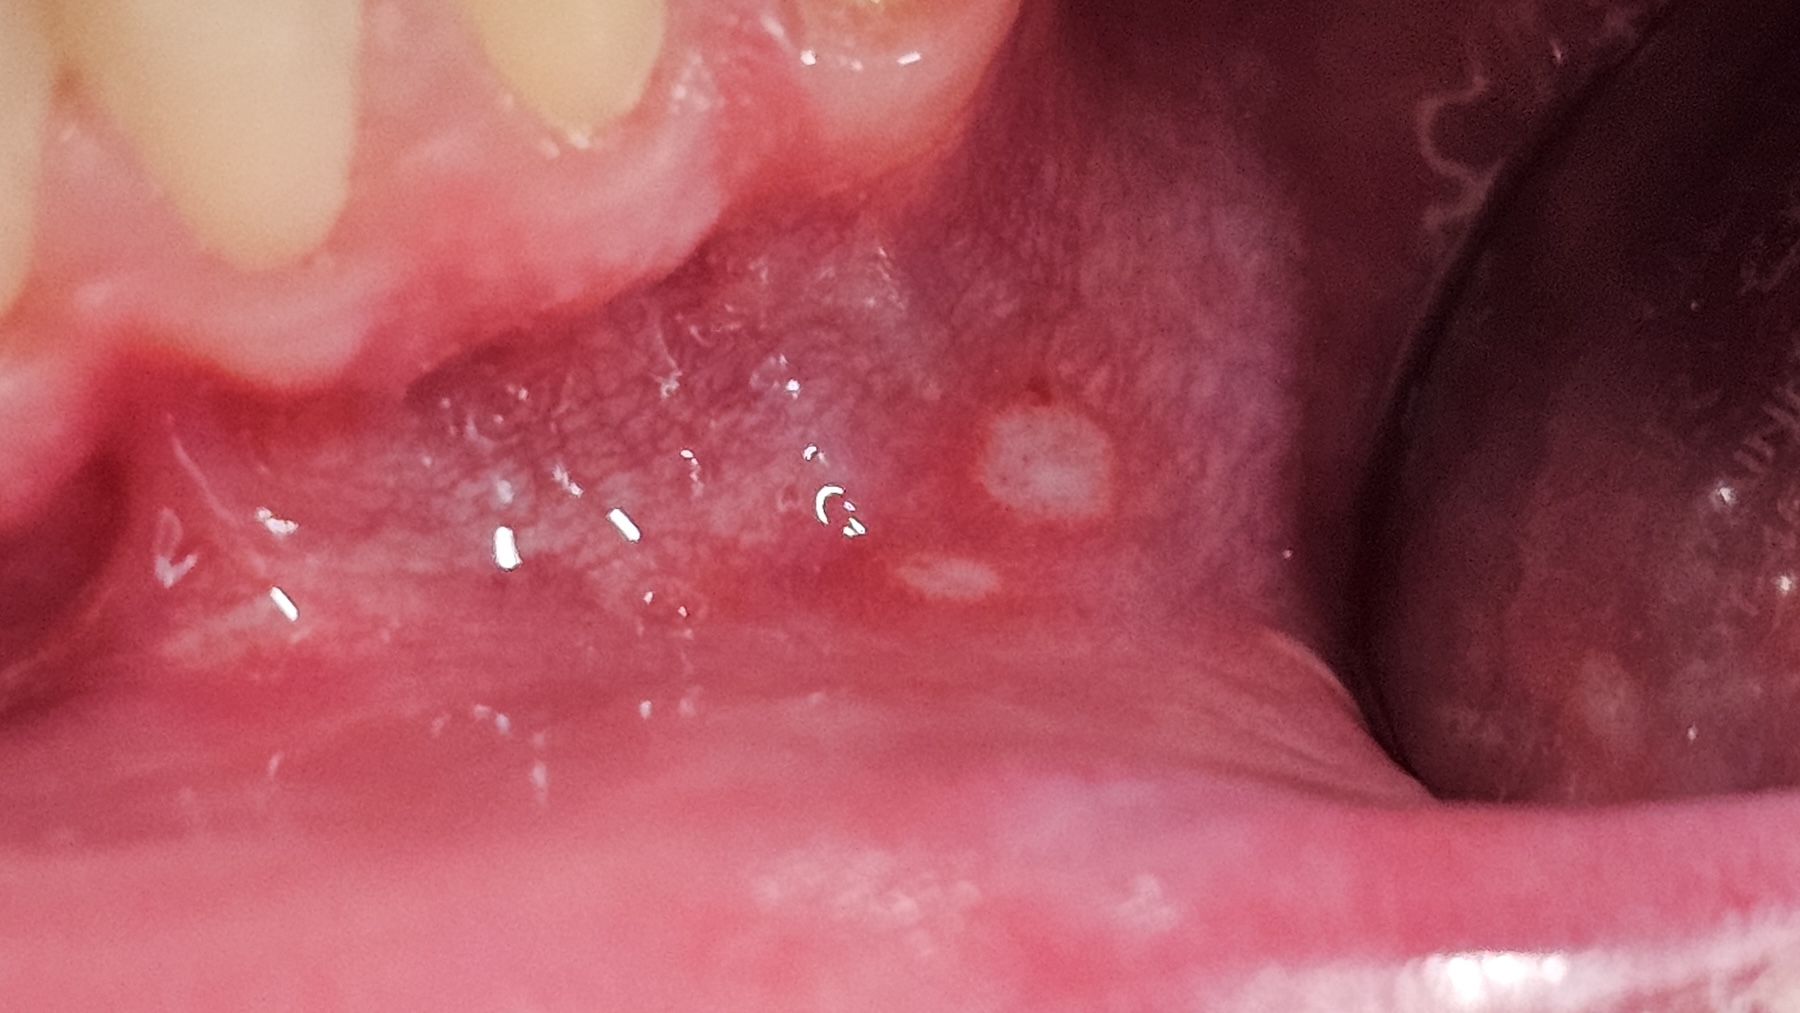

Habituelle Aphten sind schmerzhafte, kleine Geschwüre der Mundschleimhaut mit typisch rundem oder ovalem Erscheinungsbild. Sie zeigen sich als weißlich-gelbe, von einem roten Entzündungssaum umgebene Läsionen. Mit einer Größe von meist 2-10 mm treten sie häufig an der Innenseite der Lippen und Wangen und am Zungenrand auf. Am harten Gaumen und am festen Zahnfleisch treten sie nicht auf. Aphtenähnliche Geschwüre an diesen Stellen sind meist bestimmten Erkrankungen (Herpes u.a.) zuzuordnen.

Aphten der Wangenschleimhaut